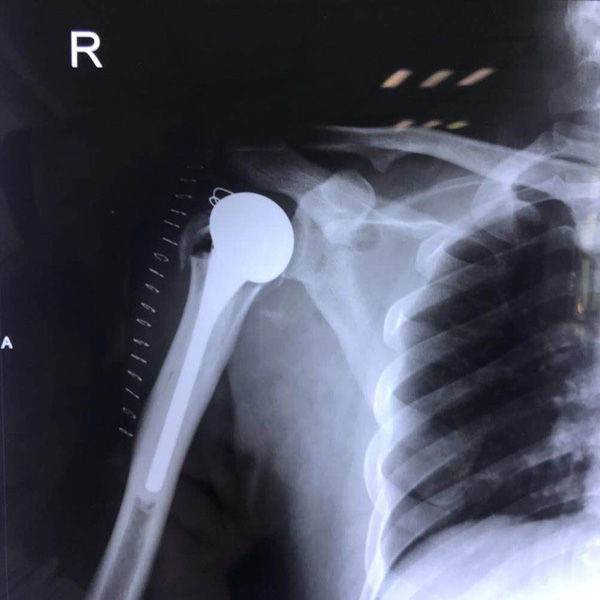

右側(cè)肱骨頭置換

患者郭某,男,40歲,因嚴重車禍導(dǎo)致“右肱骨頭粉碎性骨折”,一般的手術(shù)很難將粉碎的骨折塊拼接起來,即便大致的拼接起來,因為骨面的不平......